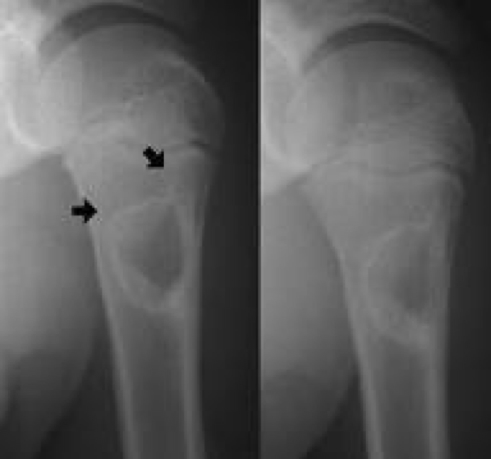

- X-ray:

- Hollow, radiolucent cavity within metaphysis